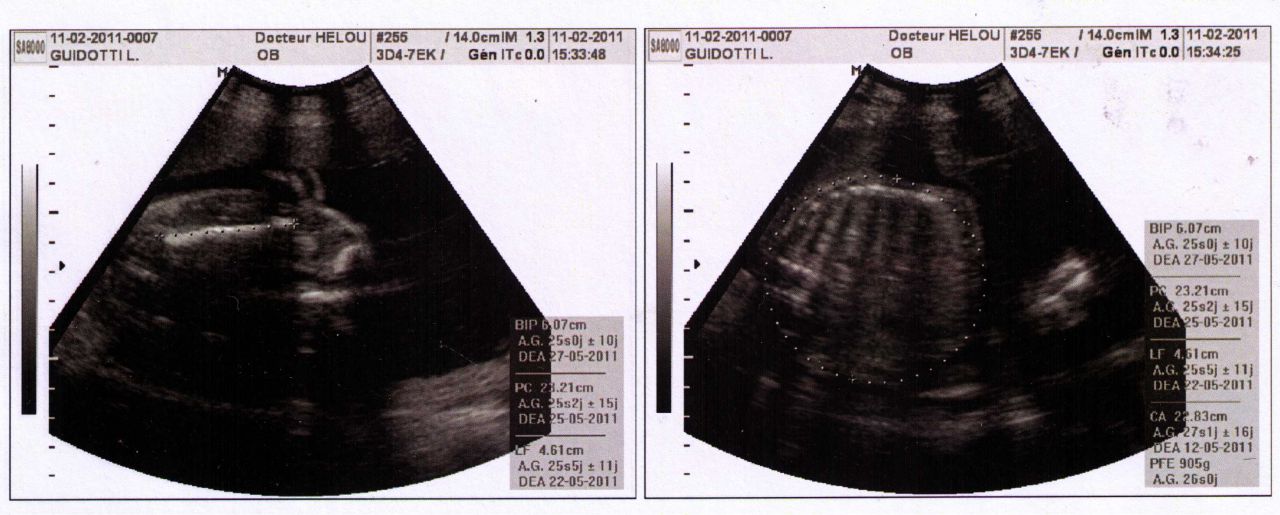

| Dire merci | aline: exact nos bébés pour la même date sont identique...peut-etre garçon, peut-etre grosse fille lol! moi je suis née avec 2mois d'avance et 2.900kg cheri, à terme avec 4 ou 5kg ![]() laetitia:ton roti!! oui c'est une approximation! mais ne t'inquiete pas mange! bébé à besoin!!! si il prends c'est qu'il en a besoin!![]() effectivement tu accoucherai fin mai entre le 12 (comme moi et le 27)après il y a aussi des probalités de faire de la retention d'eau regardez vos cheville et appuyer avec un doigt; si ça devient blanc c'est de l'eau donc ça sera perdu avec l'accouchement![]() laetitia: selon les mensurations de ton bébé tu serais à 25semaines ![]() Perimetre cranien:23.21cm longueur femur: 4.61cm Message édité le 13/02/11 à 14:26 |

| Dire merci | BIP: diametre d ela tete PC: perimetre cranien Perimetre abdominale: CA (je pense) taille femur:LF |

| Dire merci | fait pas un kilo mon roti, 905 grammes ))) pour 30 cm !Après tous le monde me dit que c'est grossssssssss ! mais mon gygy a dit que c'était un beau bébé... Après mon premier faisait 3k450 né 3 semaines avant terme... Je vous dis pas, j'avais acheté du 0 moi !!!! il rentrait pas dedans !!! |

| Dire merci | Je suis allée faire des recherches ! vous me perturbez !!! (ai je un alien dans le bide ? !) Après il parait que ce n'est qu'une approximation. Alors, j'ai fais l'écho a : milieu de 25 SA. Donc écho faite dans le 6e mois de grossesse. Après du coup, j'ai cherché les kilos des petit dans le bidou (statistiques car pour bébé en fin de grossesse a 3k200. 25 SA / 23 SG 28 cm 560 g ... il est plus grand et plus gros... du coup... Donc, soit je ne sais pas calculer a combien j'en suis )) soit ya un monstre dans mon ventre !!!! et gygy n'a pas voulu me le dire !! ![]() |

| Dire merci | ![]() Mesures du gigot !!! C'est bien 905gr... Mais du coup ma date d'accouchement bouge... ![]() Les pros des échos ? ça veut dire quoi ? C'est au choix ? |